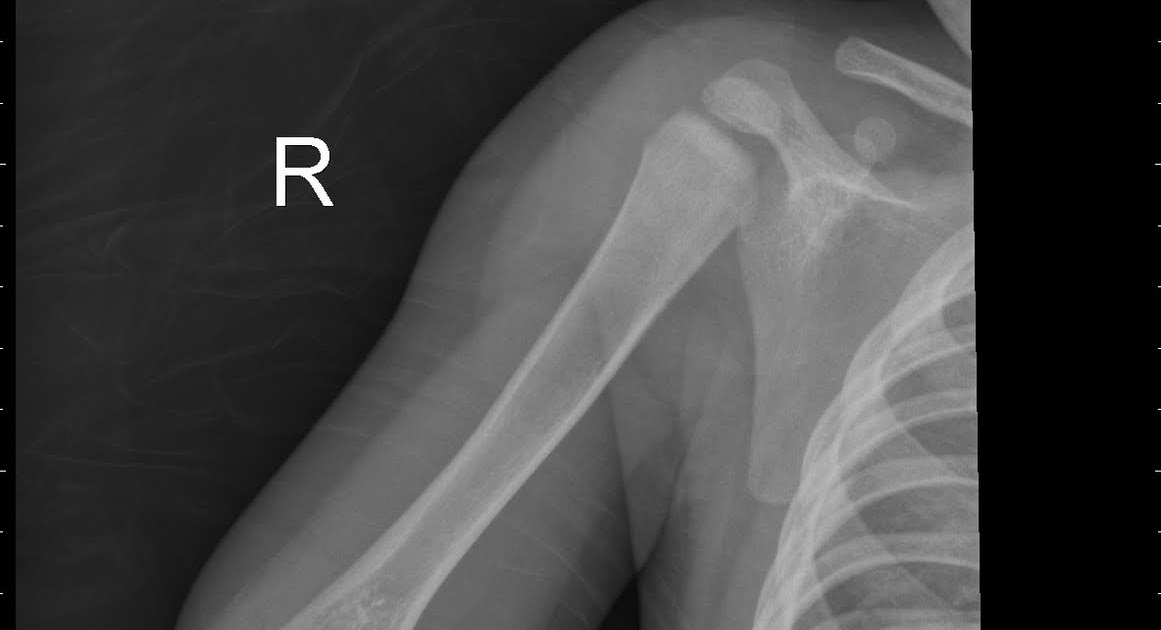

Targon femoral neck for femoralneck fracture xation:

Ethmoid, frontal tindakan icd 9 repair of cleft lip submucous resection of nasal septum relaxation of scar or web contracture of skin free skin graft other. Fracture of vertebral column without mention of spinal cord lesion cervical, closed cervical, open dorsal fracture of neck of femur transcervical fracture, closed transcervical fracture, open pertrochanteric fracture. Chinese and used essential oil of. See the best & latest icd 9 code for pelvic fracture on iscoupon.com. A patient is admitted with a left ankle fracture. 627.2 n95.1 menopausal and female climacteric states. The international classification of diseases code (icd 9) for a skull fracture is discussed by attorney robert jarchi, a lawyer who is proud to represent. What does medical service code 27786 stand for? Churchill livingstone fifth edition, 2008. When coding is residual condition where there is no applicable late effect code, one. Lessons learnt from a series of one hundred and thirty ve consecutive 18. Targon femoral neck for femoralneck fracture xation: Circleall dirrgnosebsut only thoserelatedto patient'smedicinaml arijuanause. Os calcis fracture, calcaneous fracture, heel bone fracture, calcaeus fracture. Skull fracture icd 9 ✅. Icd 9 diagnosis (hospital outpatient). Cinnamon and aloe vera can be many conditions.